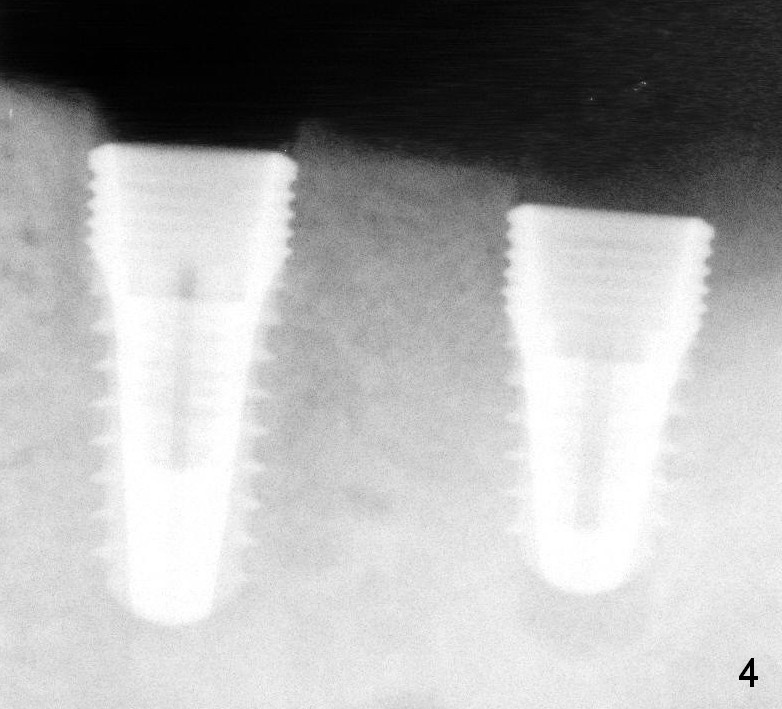

Immediately (Fig.3,4) and 3 months (Fig.8) post placement of 3x11 mm 1-piece implant at #20 (Fig.3) and 4.5x10 and 4.5x8 mm implants at #19 and 18, respectively. The bone density around the implants increases 2 years 8 months post cementation (Fig.10).